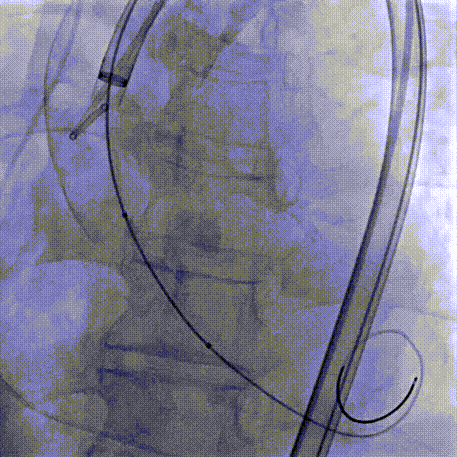

Step 2.建立大鞘通路:大鞘通过升主、边进入边加弯,避免剐蹭弓部斑块

过弓示意图